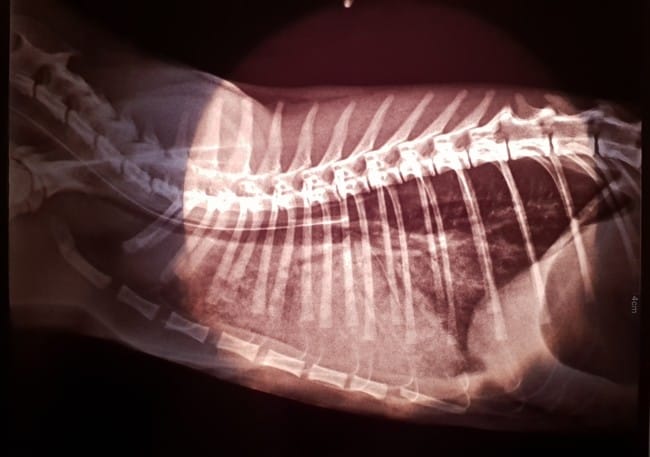

Voici des clichés de ses examens et un résumé de son comportement 1 semaine avant son départ eternel.

Je vous laisse maintenant regarder les comptes rendu de la clinique pour les jours 10 et 11. Mais en gros suite à une premiere écho le 09/12 au soir elle soufrait d'une gastro et d'une insuffisance rénal. Elle possedait un taux d'uée et de creatinine extremement elevé pour un chaton femelle. Ils ont donc essayer de la soigner mais notre puce à devollepper le 11/12 au soir vers 23h un oedeme pulmonaire aigue et ne pouvait supporter selon les veterinaires de la clinique plus trop longtemps à ses douleurs. Nous l'accompagneront le 12/12 à 00H30 pour son euthanasie.